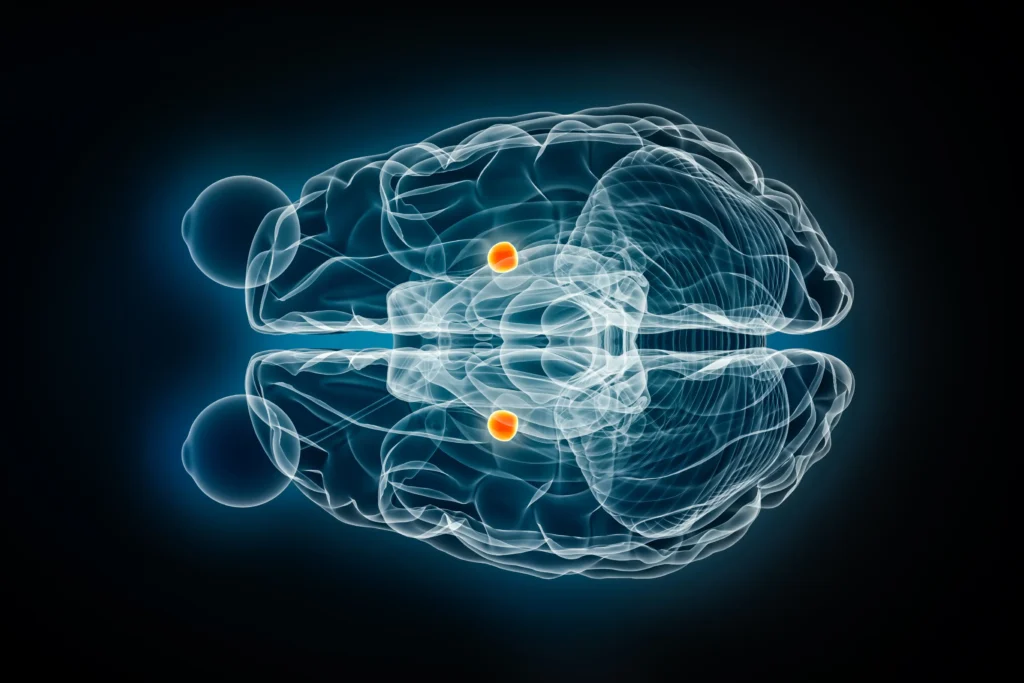

1. Amygdala

Described as the brain’s fear and emotion center, its function is to analyze threats and negative emotions and to activate involuntary physiological responses like palpitations and sweating.

In this context, MRI studies have shown increased amygdala activity in patients with anxiety compared to healthy individuals. Due to this hyperactivity, a person feels fear and anxiety even in ordinary situations. Under the dominance of the overactive amygdala, the brain begins to interpret safe scenes as suspicious and anxiety-provoking, perpetuating continuous feelings of fear and anxiety in the patient.

5. Hypothalamus and Locus Coeruleus

Known as stress response centers, the brain uses them for the early processing of anxiety-inducing factors. Each region has a distinct role: the Hypothalamus regulates the secretion of stress hormones like cortisol, while the Locus Coeruleus specializes in producing noradrenaline, which is involved in regulating attention and alertness and operates as part of the fight-or-flight response.

These two areas are activated as soon as a person is exposed to a stressful situation, and their activity is amplified, leading to symptoms such as a rapid heartbeat, sweating, and muscle contractions, which further increase the individual’s levels of anxiety and stress.